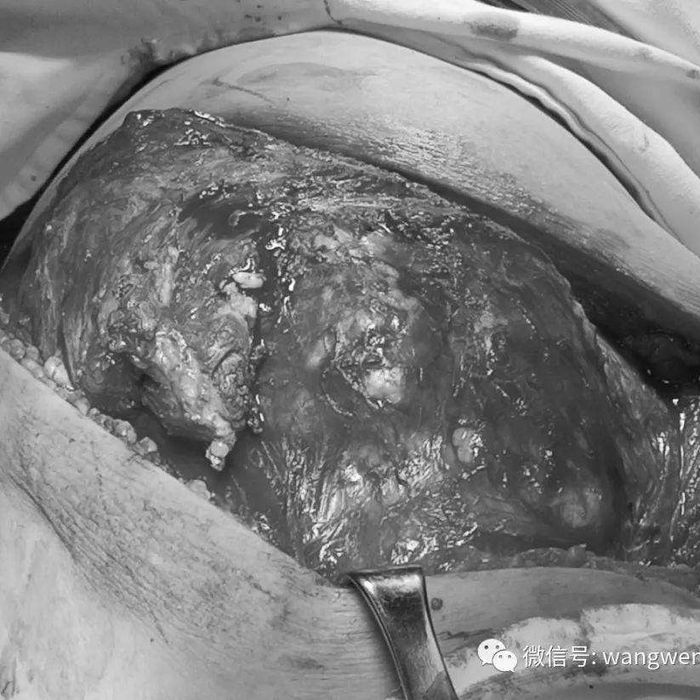

右侧胸壁有一巨大肿瘤(大小约30X25X20CM),质地较为坚硬,有压痛,移动度差。并且肿瘤已累及右侧第5、6、7、8肋骨。